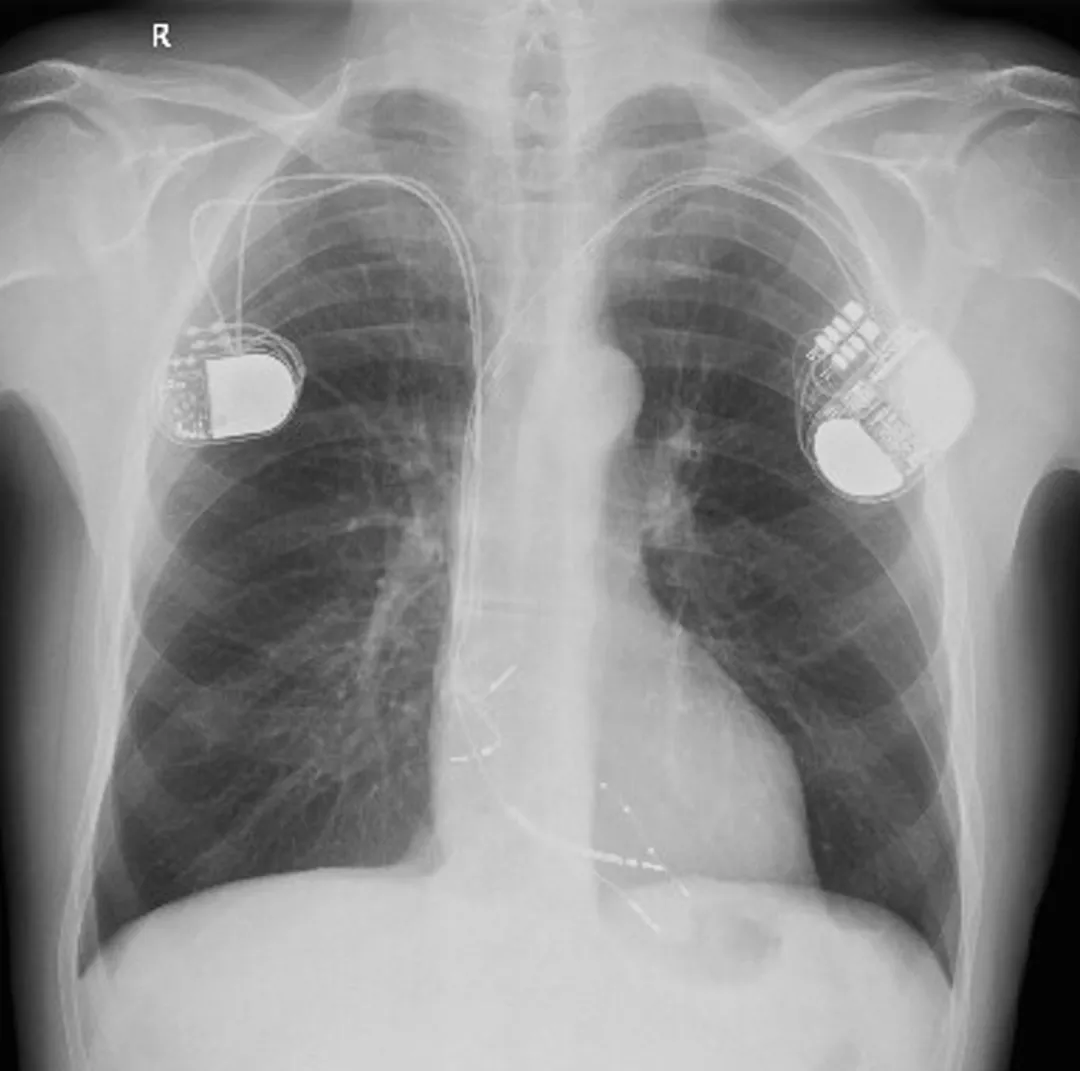

Obr. 2. Transmitrální toky při běžící komorové tachykardii.

Komorová tachykardie na EKG s frekvencí 185/minutu tak byla docela překvapením. Pacient byl hospitalizován, laboratoř neukázala zásadní patologii, v krátké anestezii byla provedena kardioverze. Ultrazvuk srdce prokázal poruchy kinetiky levé komory podobnou předchozí době, posttachykardicky ale byla ejekční frakce 35 %. Byla doplněna kontrolní koronarografie, znovu s negativním nálezem. Stávající stimulační systém byl ponechán in situ a byl přidán zleva resynchronizační systém včetně defibrilátoru a domácího monitoringu. Stranou nezůstala ani farmakologická terapie. Pacient dostal 12,5 mg spironolaktonu, 20 mg furosemidu a pochopitelně beta-blokátor: retardovaný metoprolol v dávce 25 mg. Systolický tlak při této medikaci nepřesáhl 105 mm Hg s polohovou nejistotou vždy jen ráno a po rychlém postavení. S touto terapií byl propuštěn. V ambulantní péči byl pacient stabilní, bez výboje, dle monitoringu z přístroje nebyly zachyceny komorové tachykardie. Přes výše uvedené hraniční tlaky byla s opatrností měsíc po dimisi zahájena terapie sacubitrilem/valsartanem v úvodní minimální dávce 24/26 mg dvakrát denně a přes přechodné cca týdenní období s měřenými hodnotami krevního tlaku 95/55 mm Hg se tuto terapii podařilo udržet, pacient se tlakově stabilizoval. Nedošlo k poklesu renálních funkcí ani k hyperkalémii. Pacient se vrátil k obvyklé bohaté pracovní činnosti, denně 45 minut plave. Na podzim 2021 byl ke stávající terapii přidán i empagliflozin, který pacient rovněž dobře toleruje. Furosemid užívá v režimu 1–2× týdně 20 mg, ostatní terapie zůstala nezměněna.